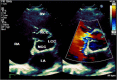

Case presentation: In this case report, we describe a 23-year-old patient with an acute onset of chest pain, shortness of breath, palpitations and dizziness starting 2 days prior to presentation to the emergency department. The patient was initially treated for presumed pulmonary embolism overnight while awaiting CTPA the next morning. However, further examination by the inpatient medical team demonstrated a continuous machinery cardiac murmur. Subsequent echocardiography demonstrated an acutely ruptured SVA with shunting to the right atrium. Emergency surgical repair resulted in an excellent outcome for the patient.